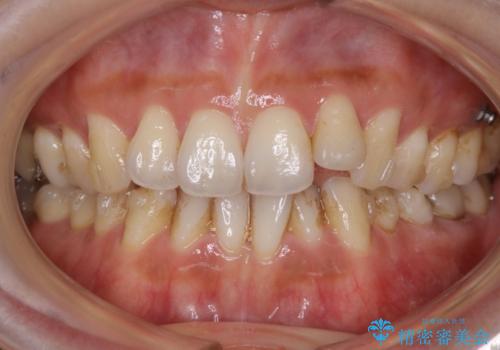

- 歯のガタつきによる見栄えや清掃困難を主訴にご来院されました。

左側の噛み合わせは上の歯が前方に寄ってきてしまっていることが原因のズレがありました。

ガタつき自体は歯列の幅の拡大やディスキング(IPR)でほとんど解消可能でしたが、噛み合わせのズレは歯の移動が必要だったため、左上にマイクロインプラントを使用し噛み合わせの改善とガタつきの解消を同時に進めるという方針をとりました。